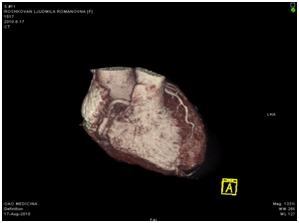

МСКТ коронарных артерий от 08.2010

Ствол ЛКА широкий, имеет ровные контуры, не стенозирован. ПНА в проксимальном сегмента имеет неровные контуры за счет кальцинированных и частично кальцинированных бляшек, просвет артерии на этом уровне сужен до 30-50%, в среднем сегменте определяется ряд пристеночных и циркулярных мягких бляшек, со стенозом артерии до 60-75%, дистальные отделы артерии малого калибра, плохо заполняются контрастным веществом. ОА нормального диаметра, заполняется контрастным веществом без признаков гемодинамически значимого стеноза. ПКА нормального диаметра, в проксимальном сегменте имеются смешанные частично кальцинированные бляшки, стенозирующие просвет до 30%, в среднем сегменте визуализируется пристеночная смешанная бляшка, стенозирующая просвет до 50-70%, дистальный сегмент не изменен. Правый тип коронарного кровоснабжения.

Трехмерная реконструкция